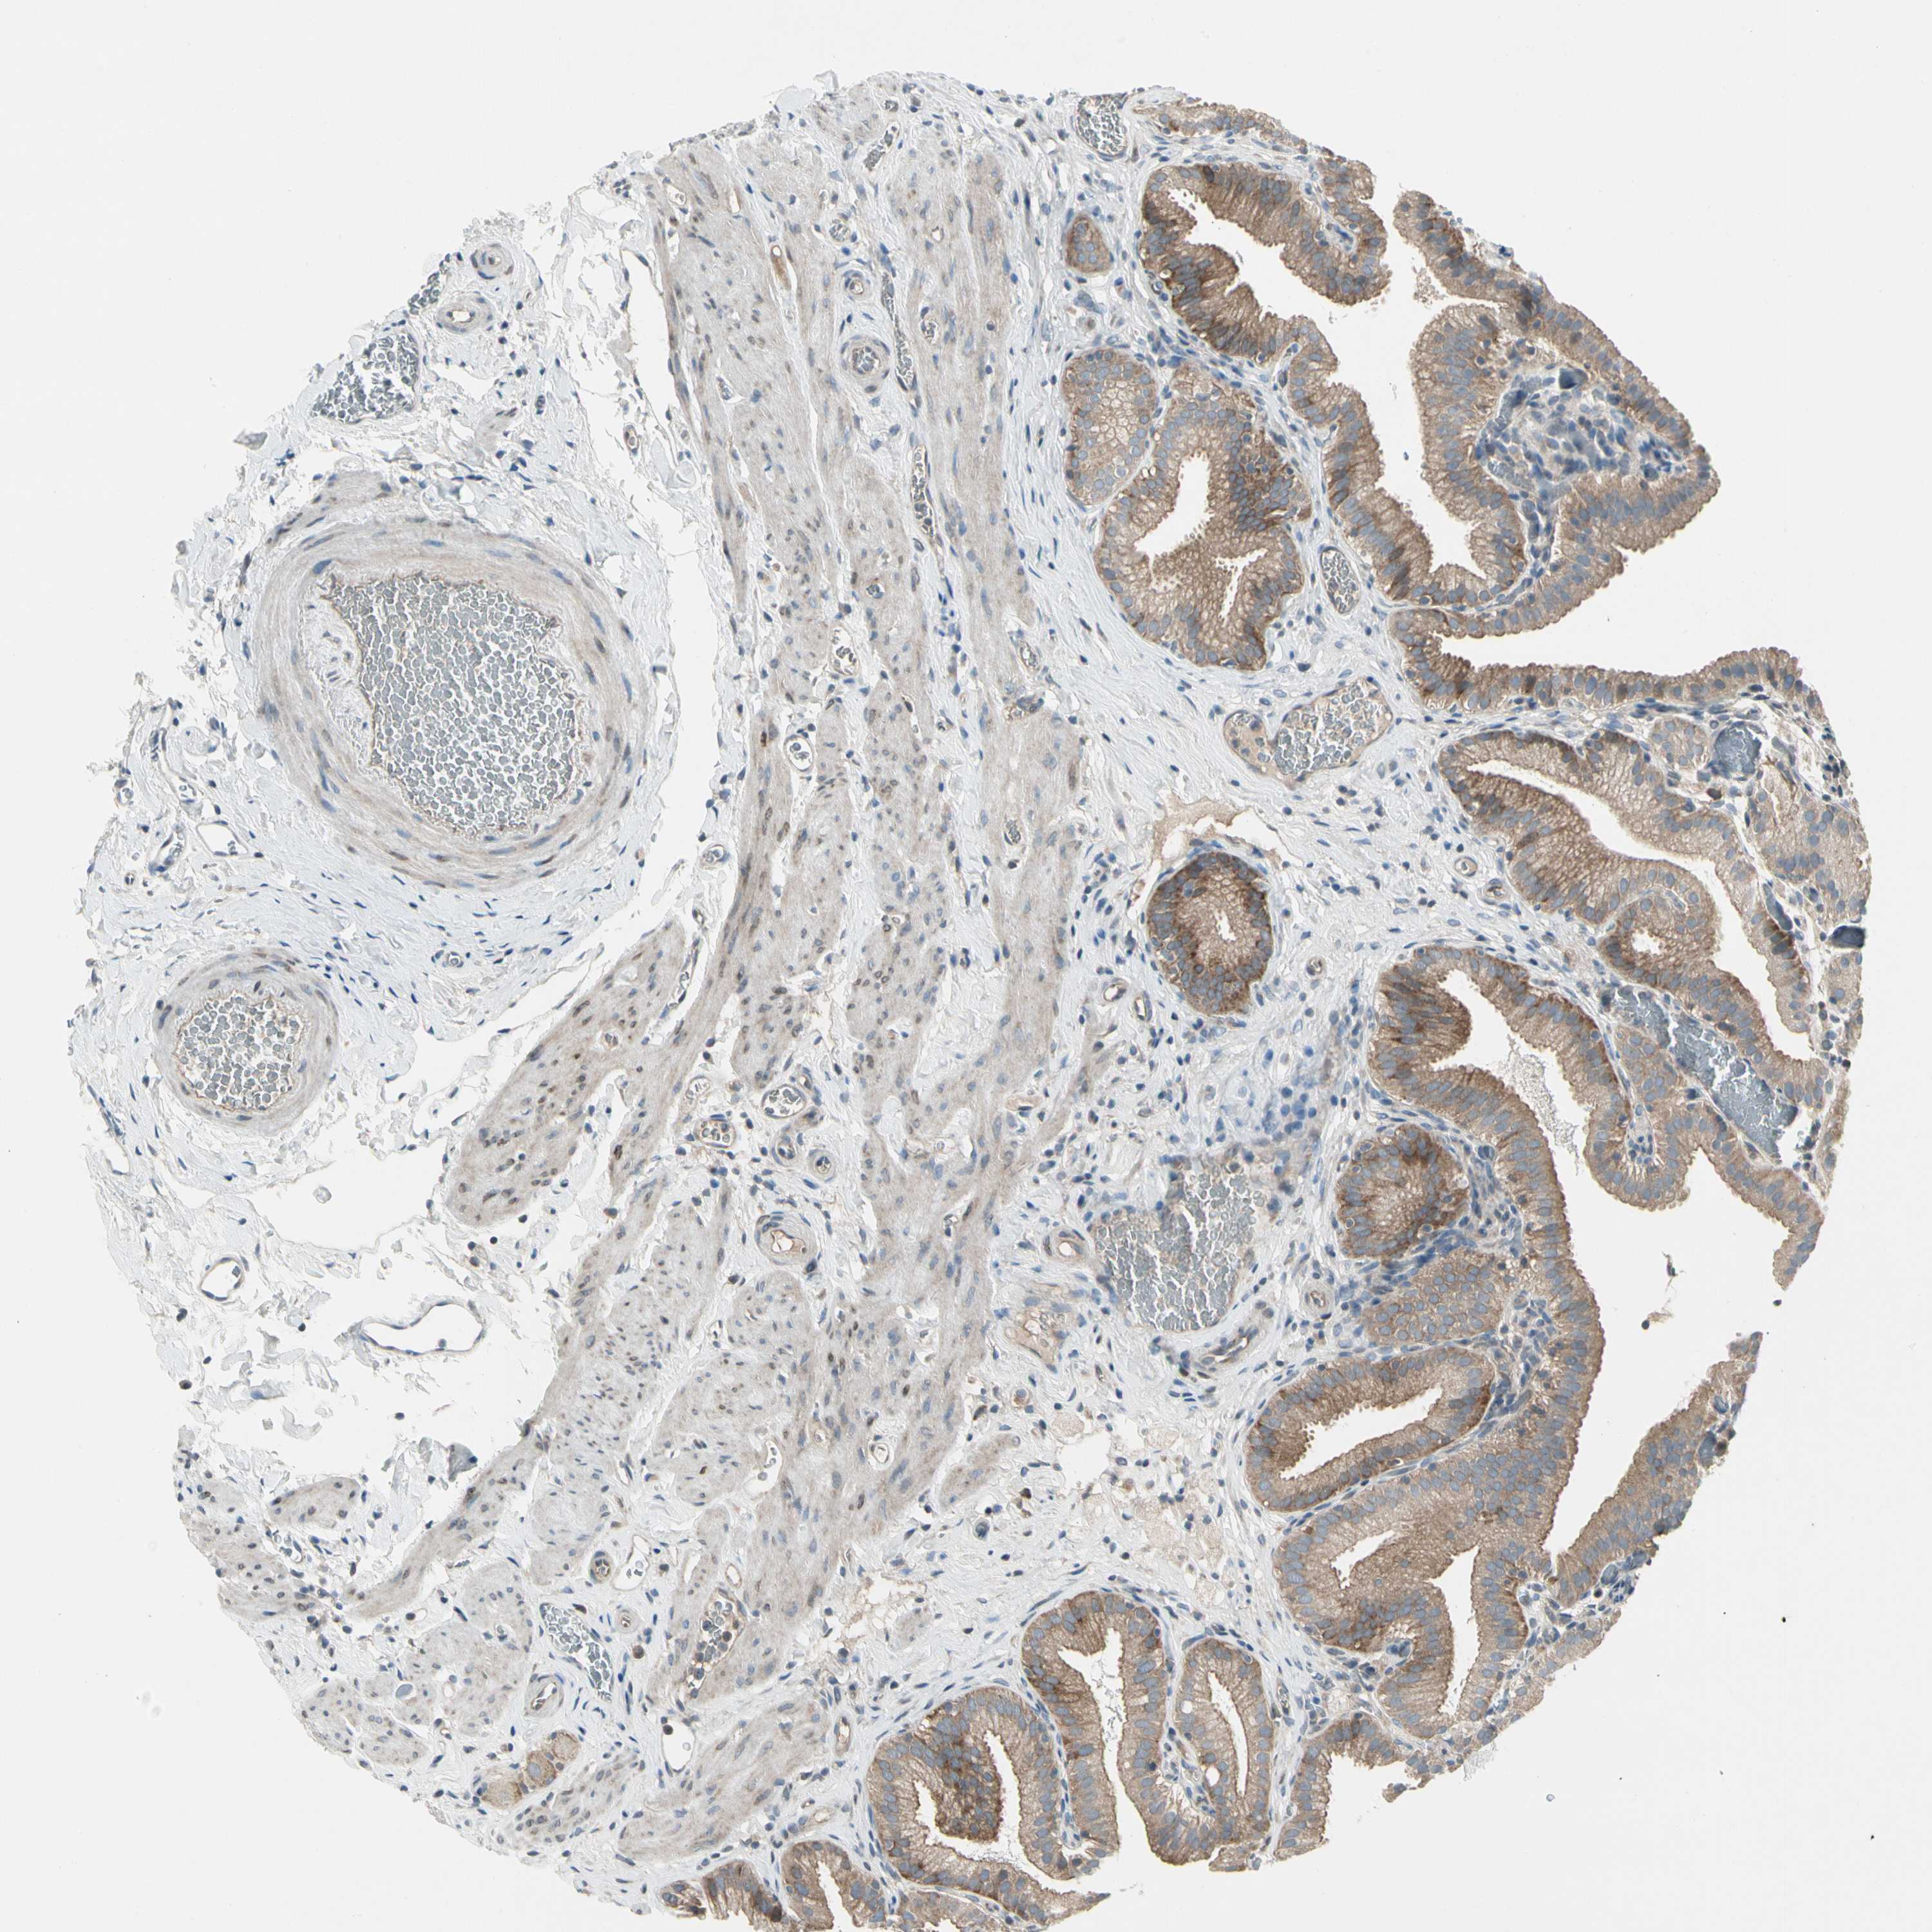

PANK2